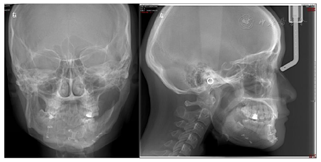

口外检查(图1):

正面观:下颌不对称,颏部右偏6 mm,微笑时露齿不足,咬合平面左低右高。

侧面观:直面型,双侧下颌升支形态不一致。

开口型左偏,开口度正常。

头颅正、侧位片检查(图4):治疗前头正片显示下颌右偏,治疗前头侧片显示骨性Ⅰ类均角。